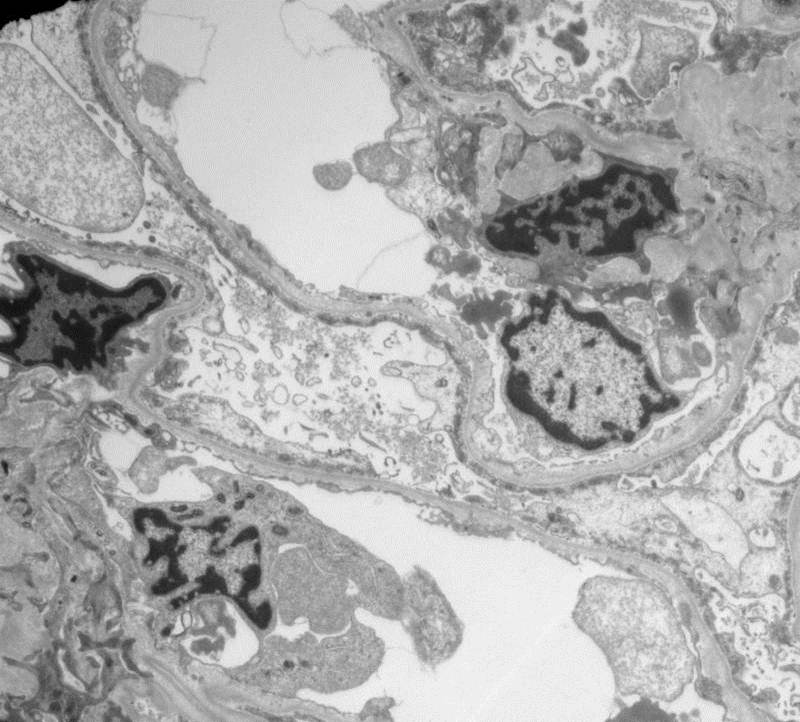

EM showed diffuse effacement of the foot processes consistent with minimal change disease. But, why did she have hematuria?

The answer is revealed by looking closer at the basement membranes. The harmonic mean thickness of the BM was 196nm which is diagnostic for thin basement membrane disease. The hematuria in this case was a red herring – her acute diagnosis was minimal change disease and she simply had not previously been noted to have hematuria.